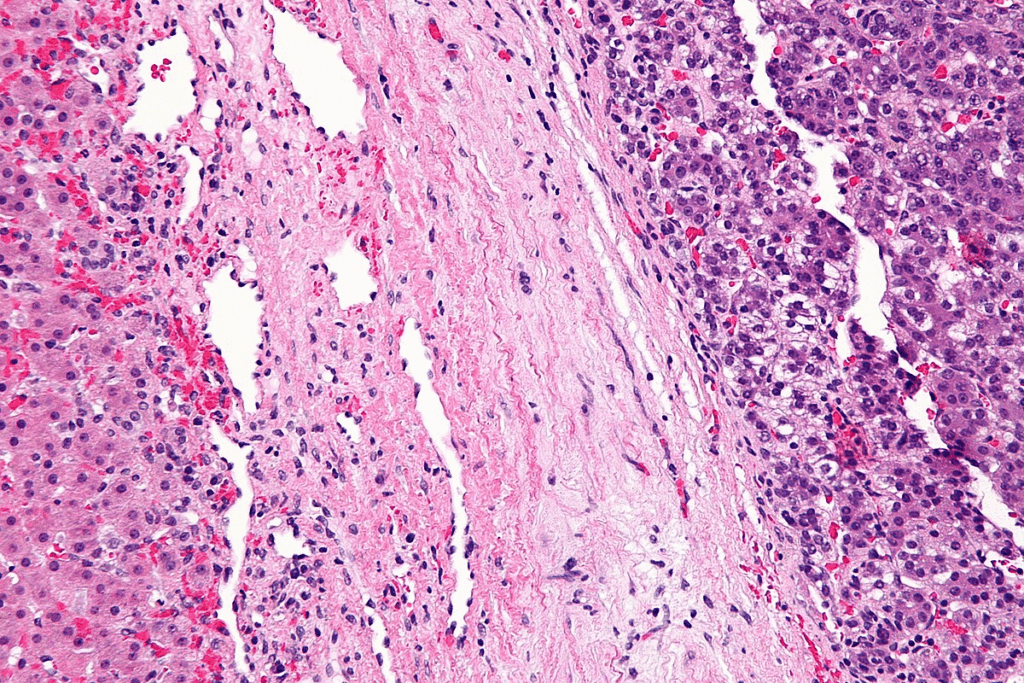

Hepatoblastoma can be divided into different types based on how the tumor cells look under a microscope. The main types are epithelial and mixed. Some research suggests that certain types might have different chances of recovery, but more study is needed.